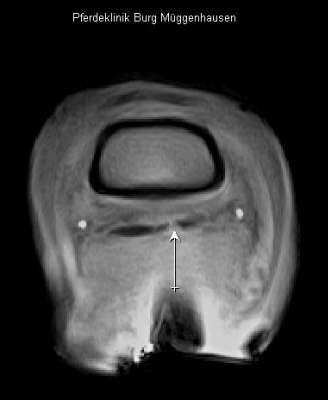

Querschnitt durch den Huf oberhalb des Strahlbeines mit deutlichem Nachweis eines Schadens der tiefen Beugesehne auf der rechten Seite des Bildes und in der Mitte